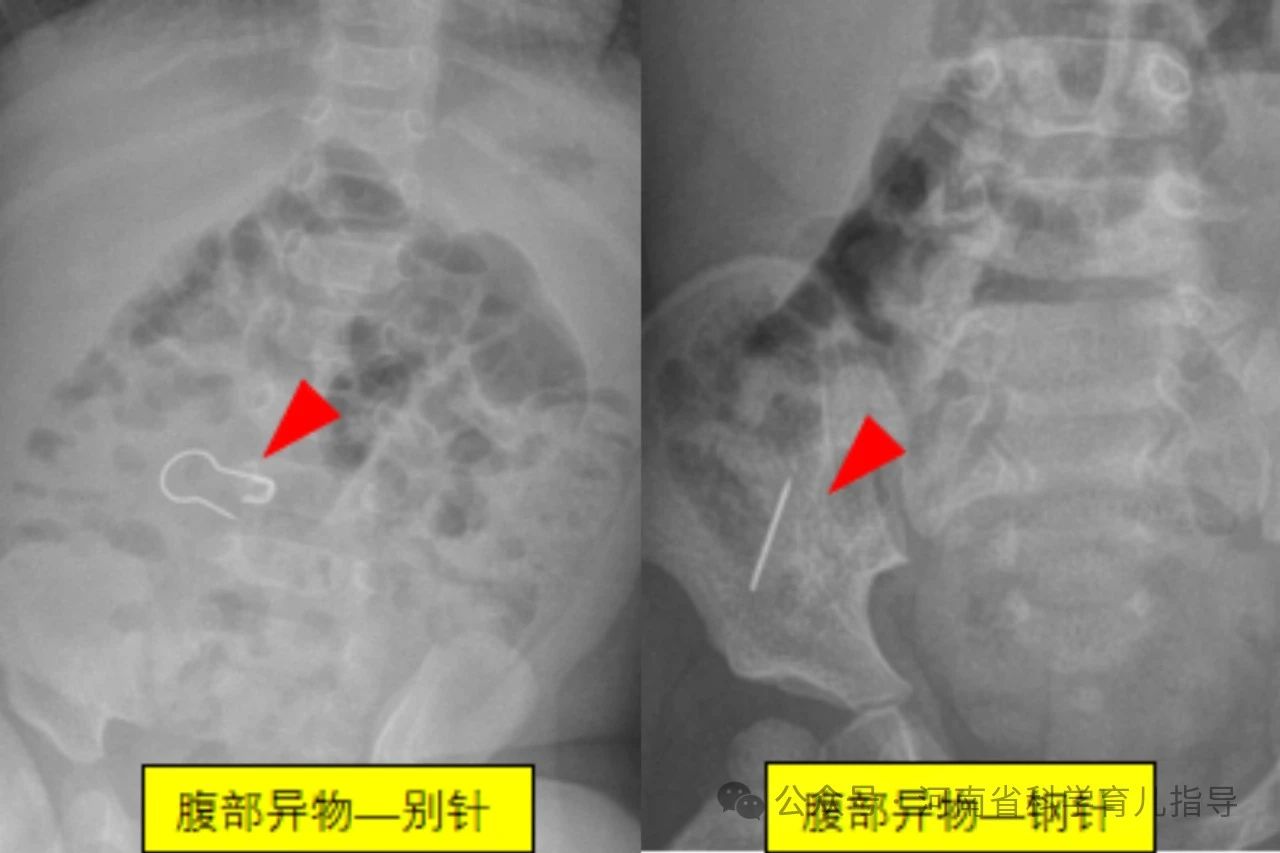

消化道异物儿童消化道异物是指儿童误吞了不能被消化且未及时排出而滞留在消化道的各种物体,文献中已报道的有硬币、果核、碎骨、电池、磁性异物、玩具、指甲、乳牙、笔头、塑料笔帽、电动牙刷头、大头针、戒指、图钉、螺丝钉、别针、纽扣、毛发等等。根据其形状主要包括以下几种,圆钝型异物如硬币,钢珠,螺丝帽,电池,棋子等圆形或者边缘比较平钝、光滑的物体,扁平状或球型。尖锐型异物如针状,钉状或者钩状物体,还有不规则型异物如女性的金属饰品发卡,生活用品如温度计中的水银等。其中形状不规则或者尖锐异物、纽扣电池、多枚磁性异物或单枚磁性异物合并金属异物发生并发症的风险较高,危险性较大。

下面来看一组尖锐型消化道异物,下图。